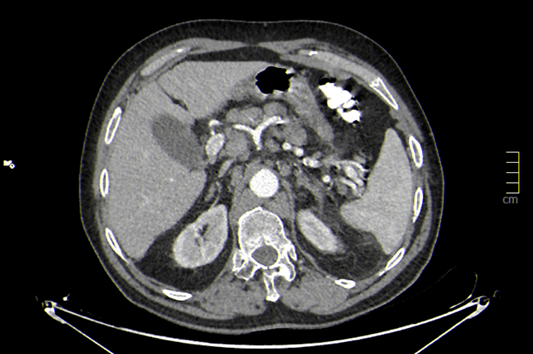

Se observan ganglios aumentados de tamaño con afectación cervical, torácica, abdominal, pélvica e inguinal.

DIAGNÓSTICO FINAL: linfoma no hodking tipo B.